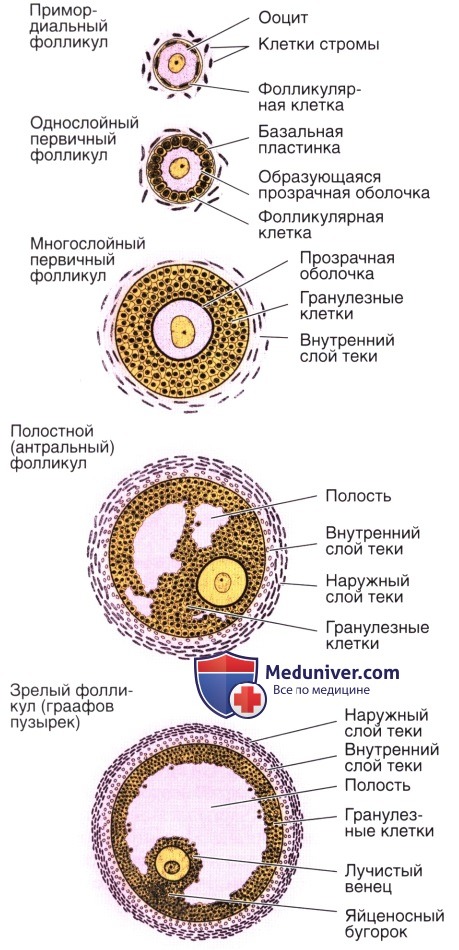

Созревание фолликула в яичнике: этапы и процессы

Раздел: Другие животные